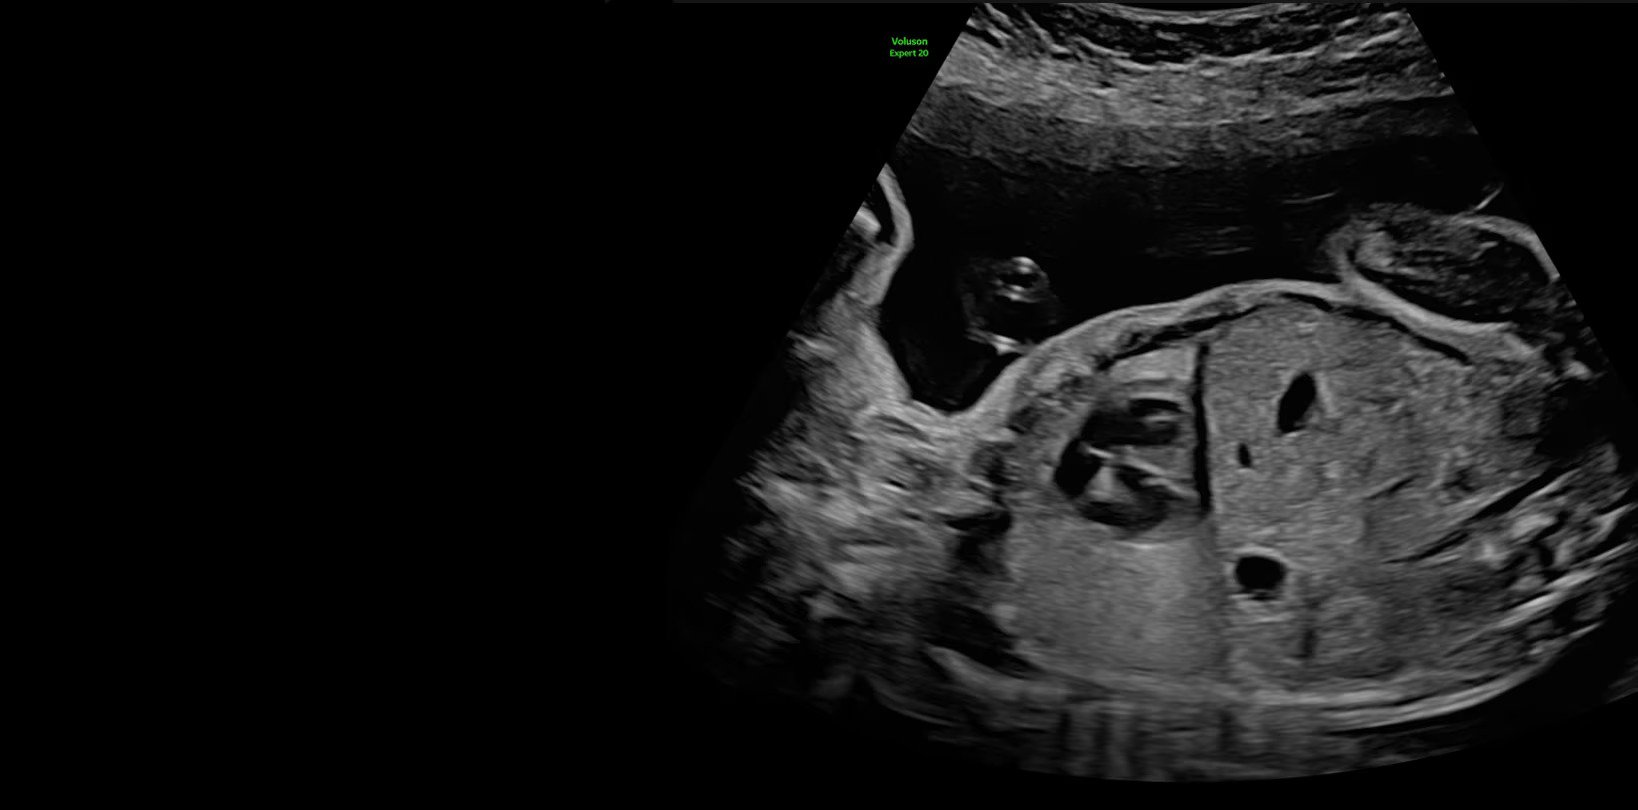

Voluson Expert 22 построен на совершенно новой высококачественной платформе Lyric Architecture, которая использует формирование луча на основе графики. Voluson Expert 22 создан для визуализации, которая сочетает в себе исключительное качество изображения, превосходные технологии объемного ультразвука и возможности искусственного интеллекта.

- Генерирует новые уровни проникновения, разрешения и частоты кадров для легкого выявления тонкой анатомии в 2D/3D/4D

- Обеспечивает однородность всего изображения с повышенным пространственным и контрастным разрешением

- Advanced STIC — расширенный программный пакет для исследования сердца плода в режиме 4D для механических и электронных объемных датчиков, включая: 1) использование цветного, энергетического допплера, В Flow — режим STIC, 2) сочетание с М-режимом — STIC-M-Mode, 3) перемещаемый источник света — STICflow, 4) программу SonoVCADHeart — программное обеспечение для исследования сердца плода в режиме 3D/4D (быстрый доступ к плоскостям сканирования) по рекомендациям ISUOG